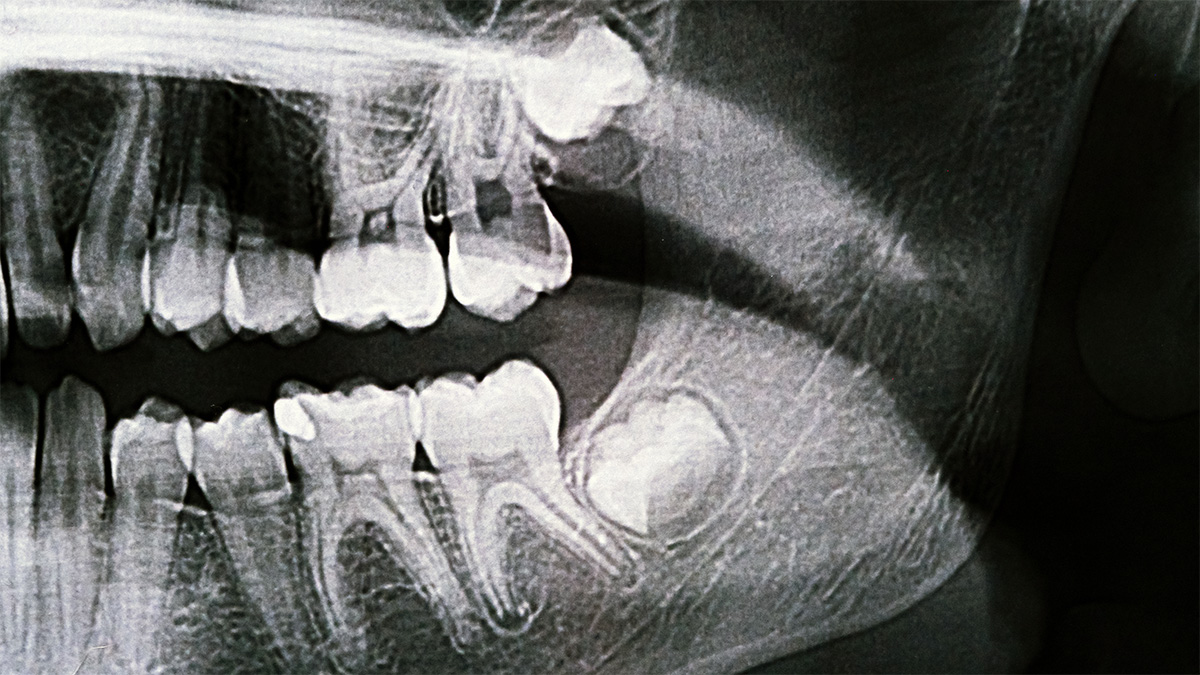

Os terceiros molares são os últimos dentes a tentar erupcionar. Em muitas bocas, já não existe espaço suficiente para eles nascerem bem posicionados. Isso pode levar a erupção parcial, inclinação, impacto no dente ao lado e inflamação recorrente dos tecidos que os rodeiam. Quando o siso nasce apenas “a meio”, cria-se uma zona difícil de higienizar, com retenção de placa e alimentos, e o resultado típico chama-se pericoronarite, uma inflamação da gengiva em torno do dente.

Retirar costuma fazer sentido quando há episódios repetidos de inflamação, dor ou infeção local, quando existe cárie no siso ou no dente adjacente associada a dificuldade de higiene, quando há reabsorção do dente vizinho, quando surgem quistos, lesões associadas, ou quando o siso interfere com tratamentos ortodônticos e com o equilíbrio oclusal de forma clinicamente relevante. Também pode ser indicado quando o siso está a provocar dano documentado no segundo molar, um cenário que pode evoluir de forma silenciosa.

A extração de um siso pode ser muito simples ou mais exigente, dependendo da posição do dente, da proximidade a estruturas anatómicas e do tipo de impacto no osso. Há casos em que o dente está totalmente erupcionado e sai como uma extração normal. Há casos em que está incluso, parcial ou totalmente, e exige abertura de gengiva, remoção controlada de osso e, por vezes, secção do dente para retirar em partes com menor trauma.

É aqui que a Cirurgia Oral faz diferença, porque o objetivo não é “tirar depressa”. É tirar de forma segura, com técnica que minimize trauma, proteja estruturas e facilite a cicatrização. Em casos selecionados, quando o siso inferior está muito próximo do nervo alveolar inferior, pode ser discutida a coronectomia, uma abordagem em que se remove apenas a coroa e se mantém a raiz, reduzindo risco neurológico em situações específicas. Não é uma solução universal, mas existe como alternativa em contextos de maior risco.